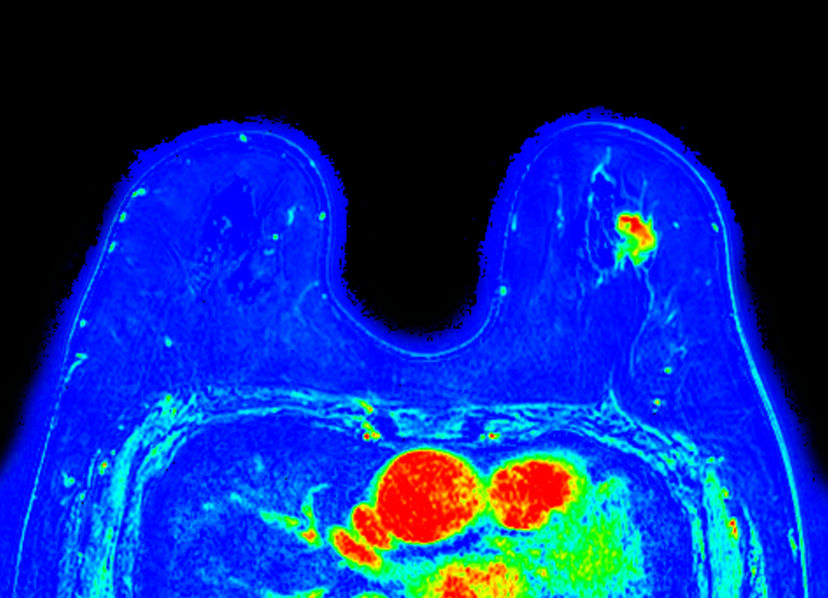

Dynamic 3D mDIXON XD - Post processing Compressed SENSE

Dynamic 3D mDIXON XD (maximum enhancement) Compressed SENSE

Dynamic 3D mDIXON XD (are under curve) Compressed SENSE

Dynamic 3D mDIXON XD (washin) Compressed SENSE

Dynamic 3D mDIXON XD (washout) Compressed SENSE